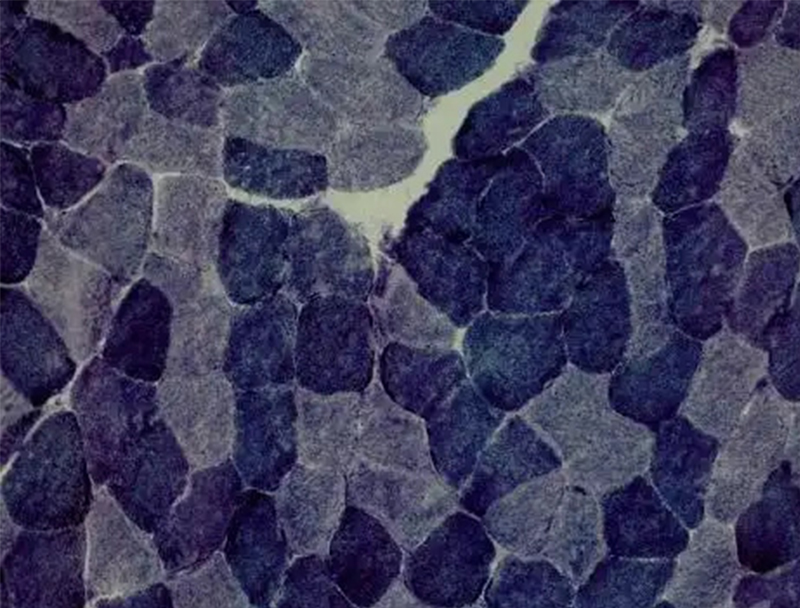

以下是關(guān)于 ATP 酶染色的相關(guān)介紹:基本原理ATP 酶是一種水解酶,可催化 ATP 分解產(chǎn)生能量。在 ATP 酶染色中,常用的是鈣鈷法,其原理是 ATP 酶水解 ATP 為 ADP 和磷酸,磷酸與鈣離子在酶活性部位結(jié)合形成無色的磷酸···